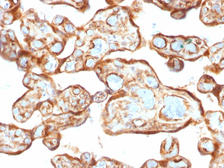

Images